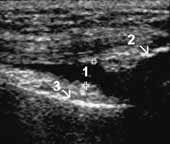

При этом в норме синовиальная оболочка не визуализируется. При деформирующем

остеоартрозе с синовитом отмечается увеличение сумки, выпрямление складок, наличие

избытка жидкости (Рис. 2). Жидкость относительно однородная. При воспалительном

поражении (при ревматоидном артрите) также отмечается увеличение сумки с наличием

избытка жидкости, но количество жидкости обычно больше, чем при остеоартрозе,

она чаще неоднородная, обычно более «гиперэхогенная», синовиальная оболочка

утолщена до 1–3 мм и более (Рис. 3).

Рис. 2. I стадия остеоартроза. Умеренное увеличение b. suprapatellaris

(1+) с наличием избытка относительно однородной жидкости, 2 — надколенник,

3 — бедренная кость.

Рис. 3. Ревматоидный артрит, III стадия. Выраженное увеличение

b. suprapatellaris с наличием неоднородной жидкости и пролиферацией

синовиальной оболочки (+).